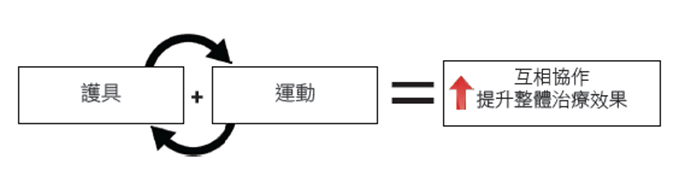

配合護具進行最精準最安全的運動: 護具和運動之間存在高度相輔相成作用,它們擁有協同作用產生相得益彰帶來更好的治療或復康效果,尤其是在創傷後癒合和術後康復,及慢性脊椎和關節疾病的治療。護具能「提供支撐」、「限位固定」、「矯形緩痛」及「解決神經受壓的痛楚」等問題,而運動則能增強肌肉力量和關節活動功能。結合適合的護具和適當的運動訓練,可以改善體感平衡和整體康復效果,並可糾正脊椎和關節錯位之彎曲問題。